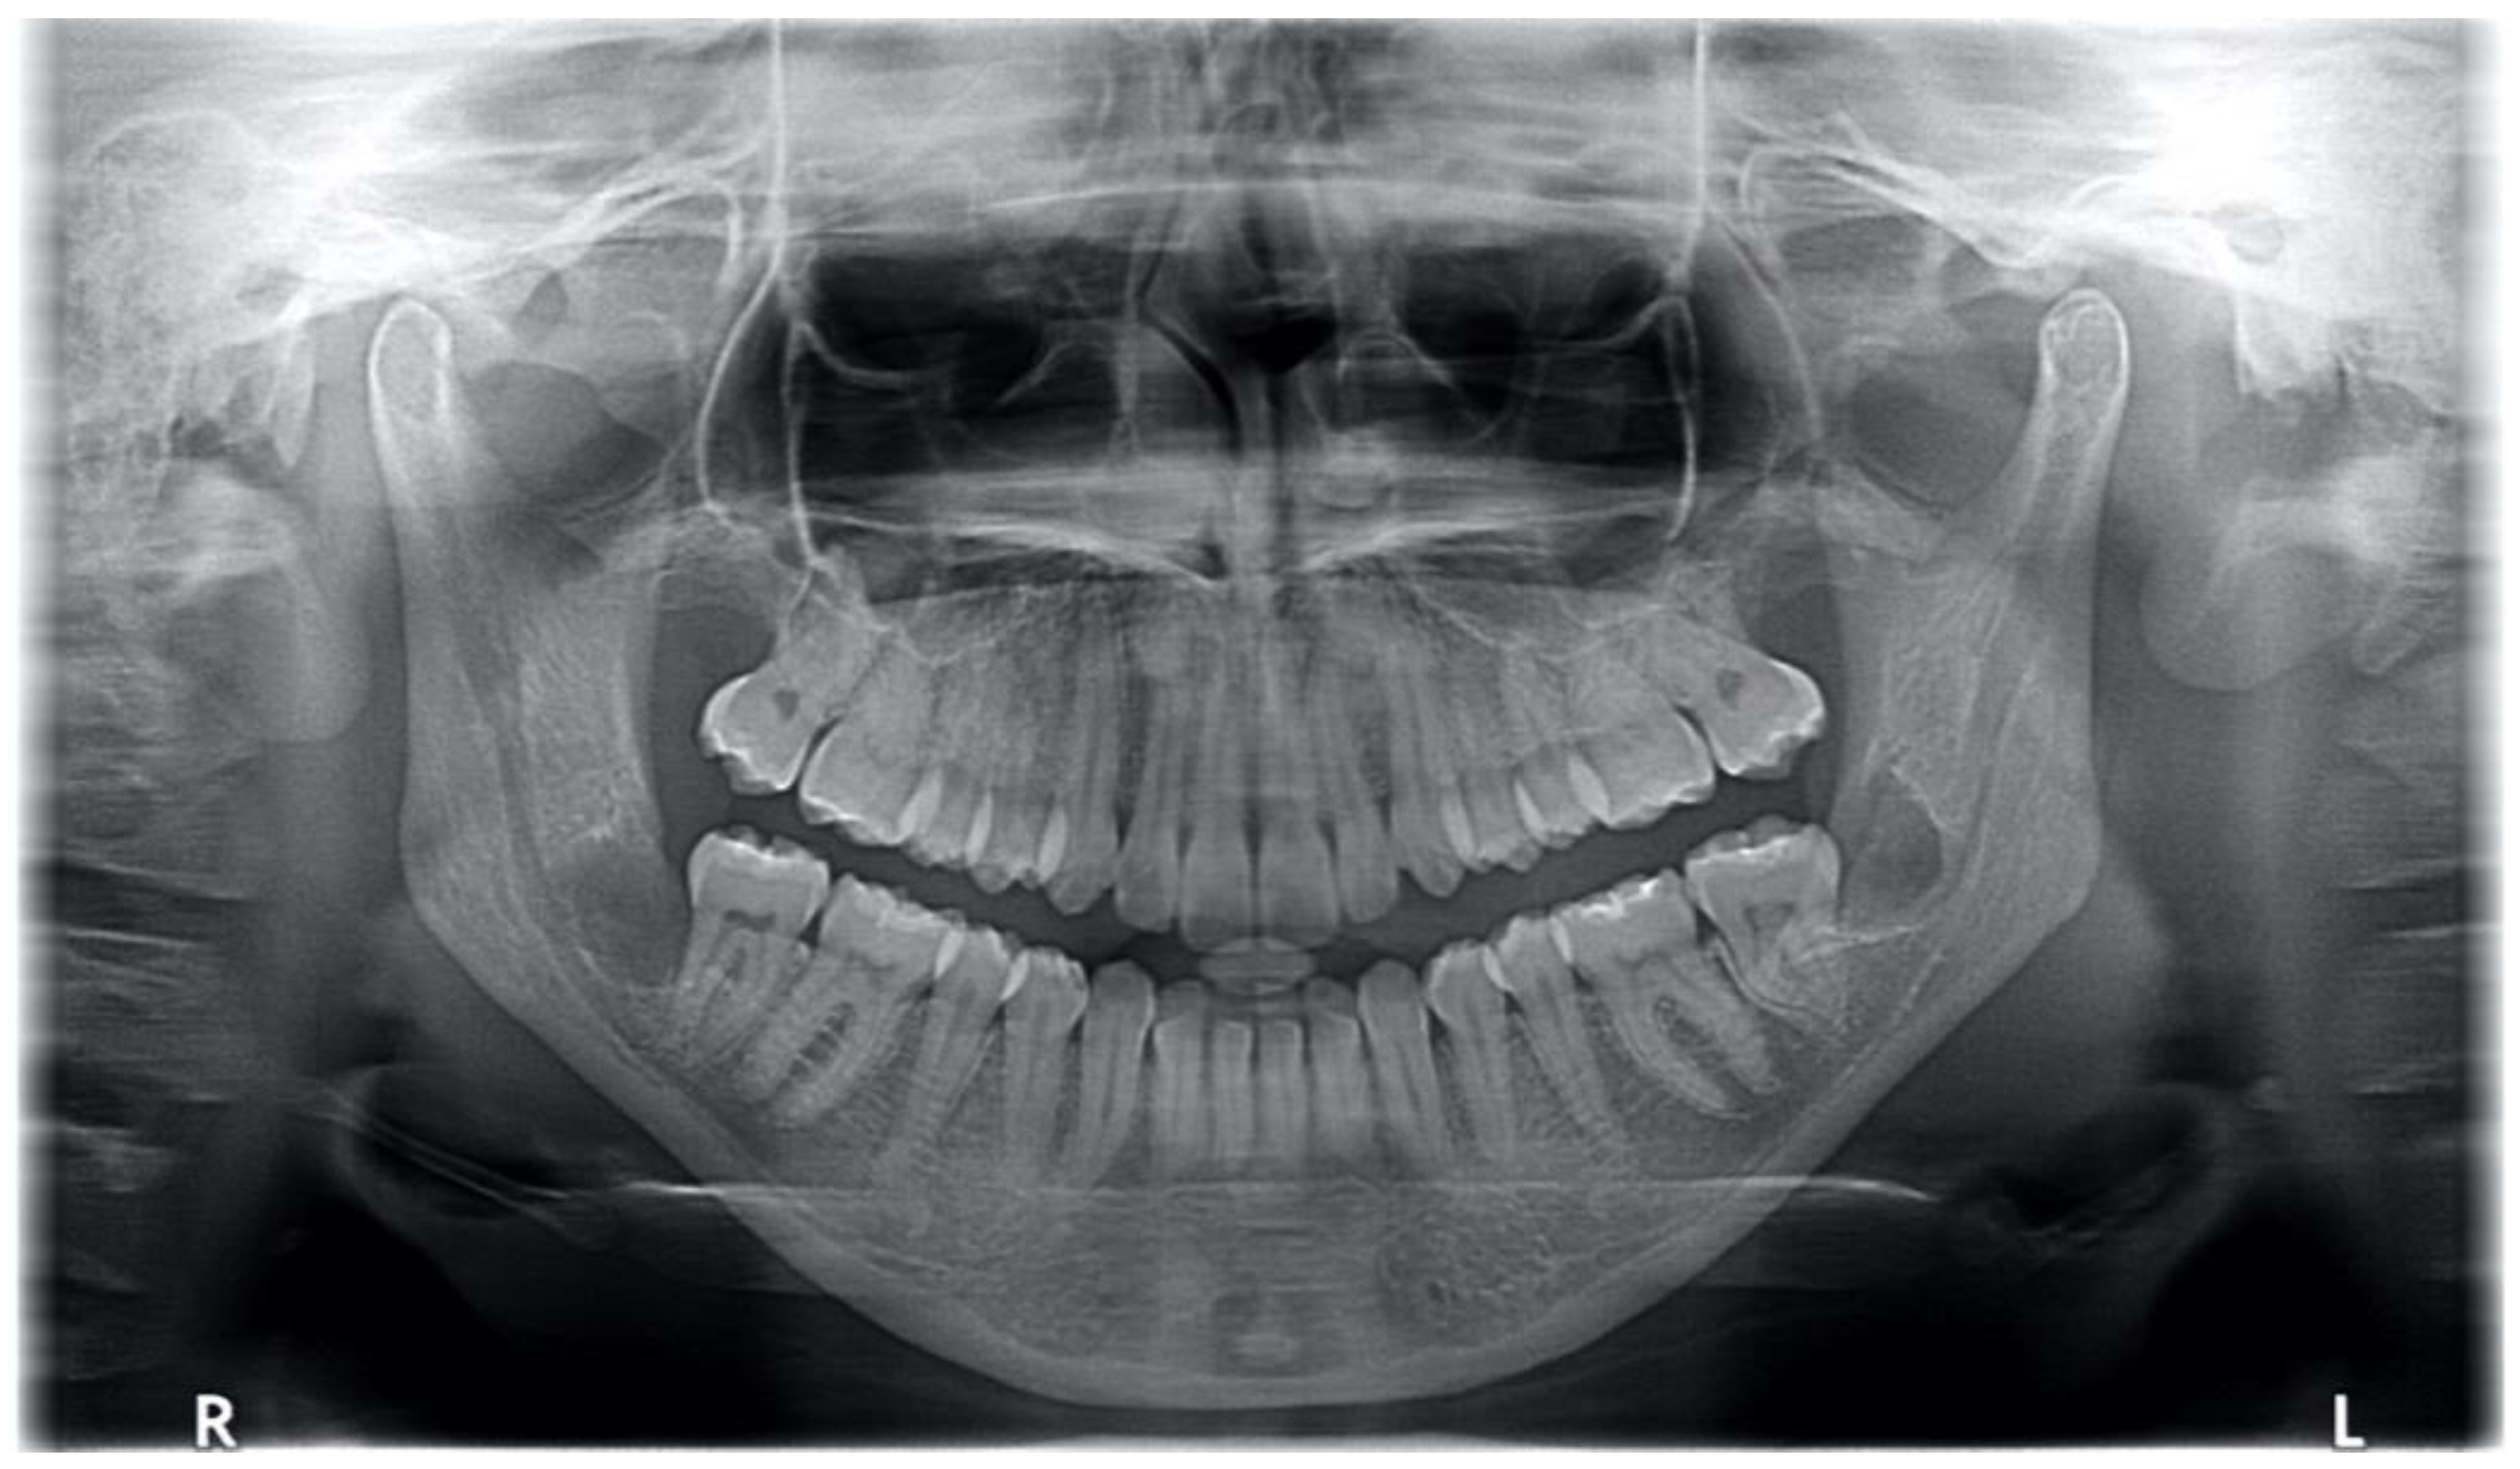

3.2. Case 2: Multi-Space Odontogenic Infection